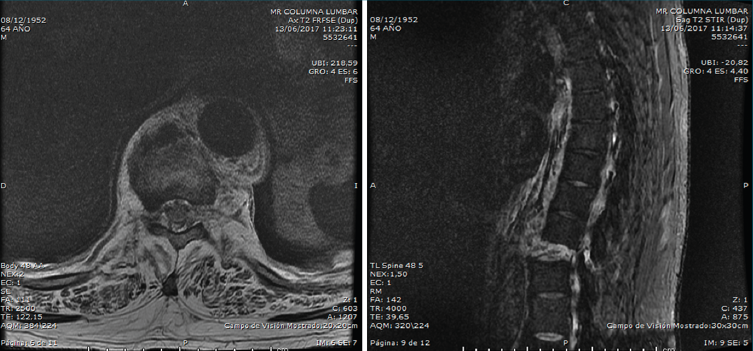

En la Figura 4 se muestran cortes de resonancia magnética (RM) axial y sagital, secuencias Stir. En el corte sagital visualizamos claramente la lesión. La columna se ha comportado como una “caña rígida” y el traumatismo ha provocado una lesión de todo el complejo posterior, con diástasis de las articulares posteriores a nivel de T10/T11, lesión completa del complejo ligamentoso posterior, progresión de la misma a través del disco y distracción anterior T10/T11.

Figura 4. Cortes axial y sagital de resonancia magnética, secuencia Stir.